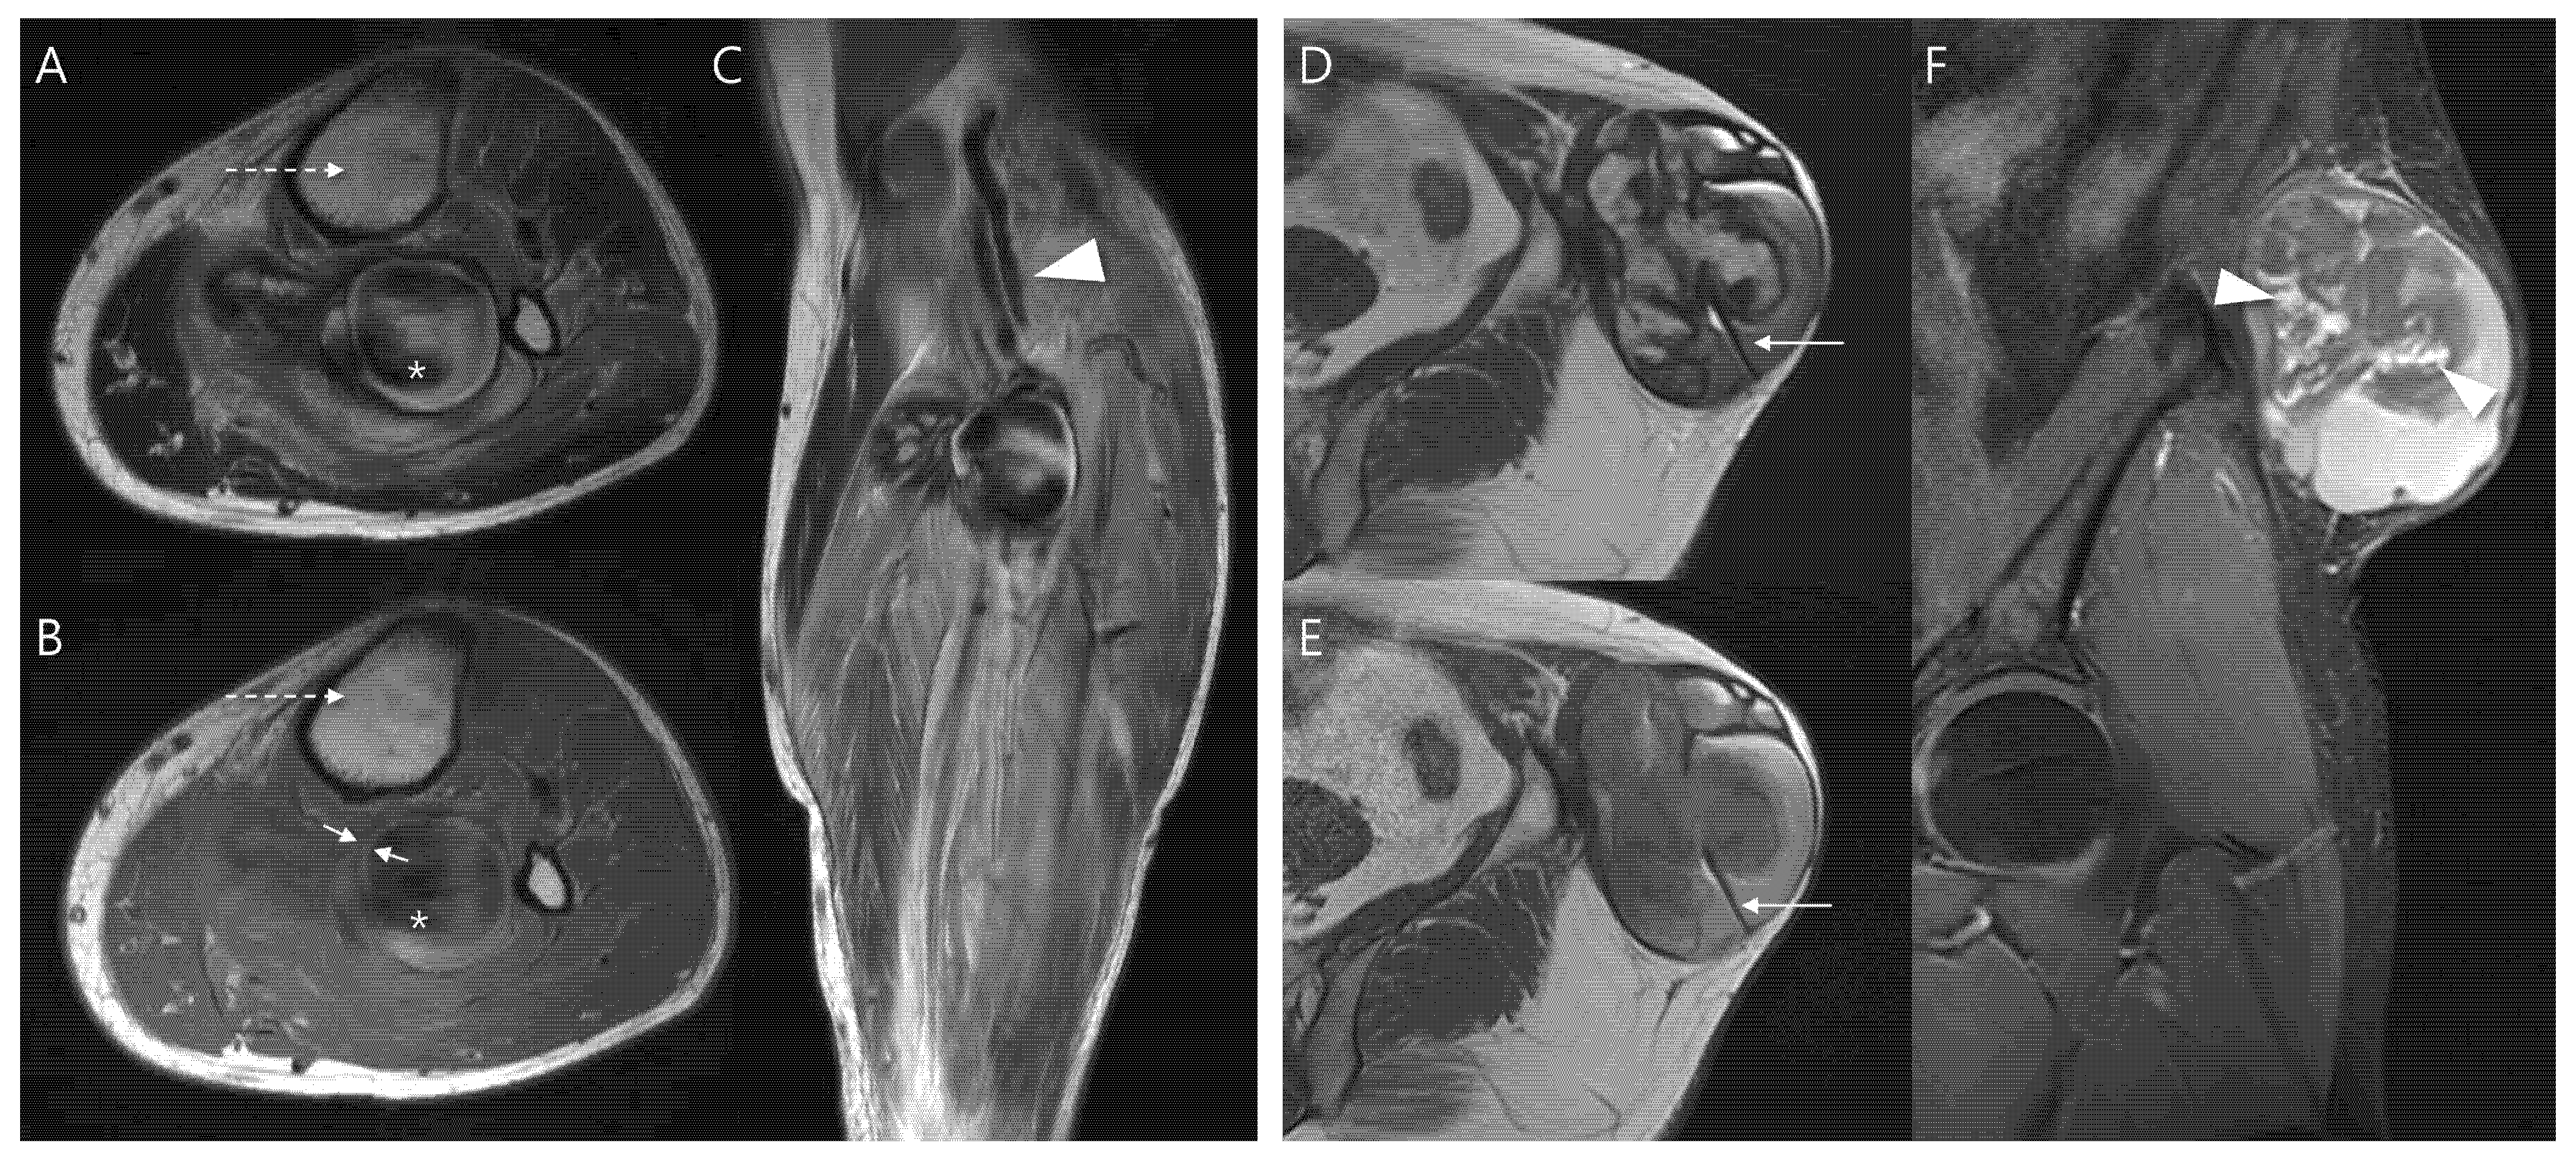

Second, the following MRI features were assessed—including lesion morphology, internal characteristics, pulsatile artifact, and relationship to adjacent structures (Figure 1). Morphology was categorized as either ovoid or multilobular in contour. Internal characteristics related to hematoma were evaluated as follows: (1) outermost peripheral low SI on T1WI—indicating a fibrous pseudocapsule with hemosiderin or collagenous tissue [22,23]; (2) inner peripheral high SI on T1WI, located just inside the low-signal rim—reflecting mural thrombus with methemoglobin [11]; (3) central high SI on T1WI—consistent with subacute/mature methemoglobin or repetitive rebleeding deposits [24]; (4) central flow void on T1WI and T2WI, appearing as a distinct signal void or markedly hypointense core due to rapid intraluminal blood flow, observed on all sequences (but most conspicuous on T2WI due to strong flow-related dephasing)—indicative of fast-flow blood [25,26]; (5) septation—representing internal fibrous septa or loculations [5]; and (6) nodular enhancement—suggesting granulation tissue or neovascularization.

Figure 1.

MRI findings of pseudoaneurysm (A–C) and chronic expanding hematoma (D–F). (A) Axial T2-weighted and (B) T1-weighted images show an intramuscular, ovoid mass with a central flow void (asterisk in (A,B), fast-flow blood), pulsatile artifact (dotted arrow in (A,B) and inner peripheral high SI on T1-weighted image (arrows in (B), mural thrombus). (C) Coronal T2-weighted image demonstrates neurovascular involvement (arrowhead). (D) Axial T2-weighted and (E) T1-weighted images reveal a multilobular subcutaneous mass with heterogeneous signal intensity with septations (arrow in (D,E)). (F) Coronal T1-weighted contrast-enhanced image demonstrates nodular enhancement (arrowheads, granulation tissue) within the mass.

A pulsatile artifact (Figure 1) was defined as a motion-related imaging artifact on MRI that arises from the periodic pulsation of blood flow, typically appearing as ghosting of SI along the phase-encoding direction and was considered as an indirect marker of active vascular flow [27,28].

Last, neurovascular bundle involvement (Figure 1) was considered positive when displacement, encasement or infiltration of adjacent neurovascular structures was observed [29].